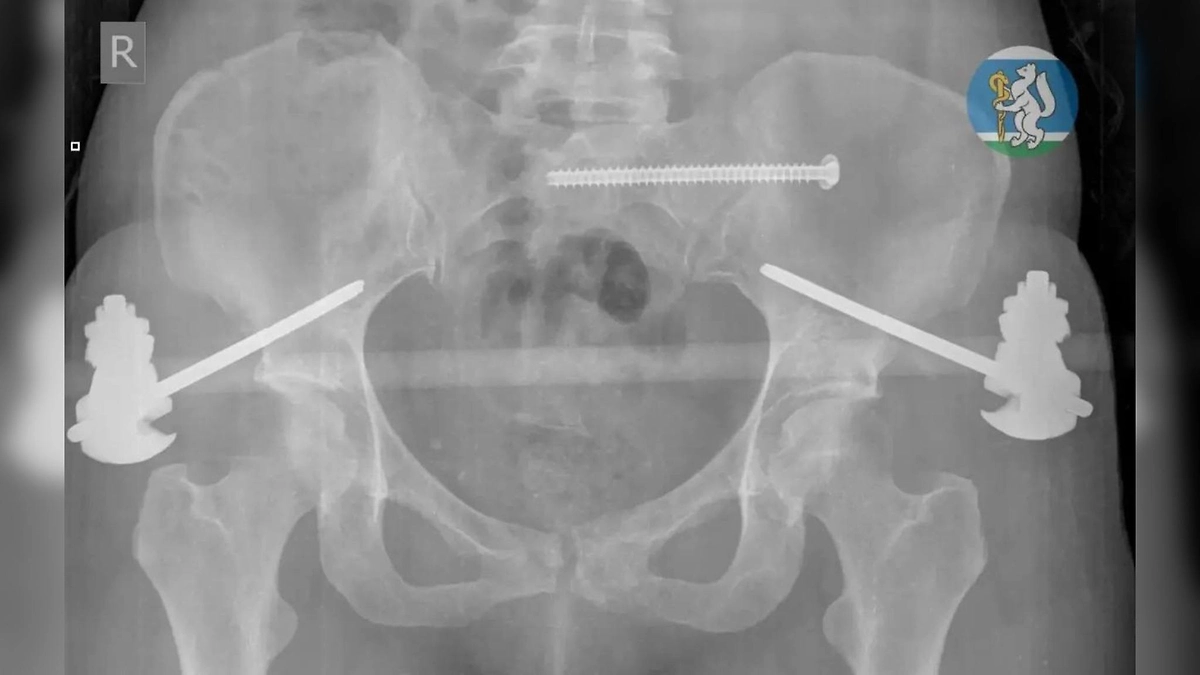

У пациентки выявили тяжёлые повреждения: травму головы, повреждение шейного отдела позвоночника, множественные переломы таза, а также повреждения грудной клетки с поражением лёгких и серьёзные переломы ноги. Специалисты отметили, что подобные травмы часто заканчиваются летальным исходом ещё до прибытия в медучреждение.

После проведения операции женщину перевели в реанимацию, где она находилась на аппарате искусственной вентиляции лёгких до стабилизации состояния. Позже её перевели в травматологическое отделение, где провели дополнительное хирургическое вмешательство. Врачи выполнили коррекцию фиксаторов и восстановление костей. В настоящее время пациентка выписана и проходит курс реабилитации.